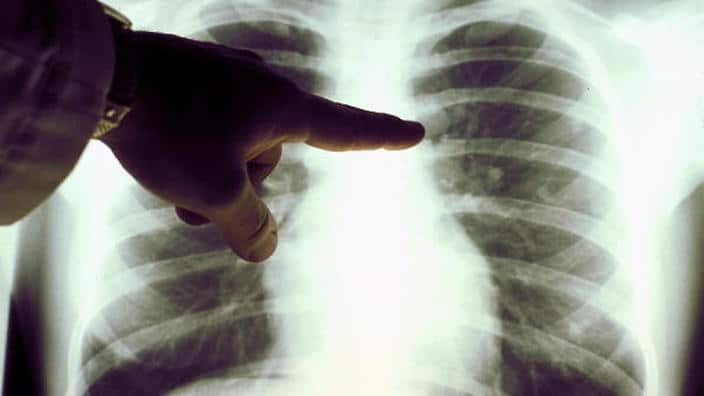

يُعد سرطان الرئة خامس أكثر أنواع السرطان تشخيصًا في أستراليا، ولكنه يسبب أكبر عدد من الوفيات لأنه غالبًا ما يتم تشخيصه بعد فوات الأوان.

وزير الصحة الأسترالي، مارك بتلر، أوضح أن هذا البرنامج يتيح لهؤلاء الأشخاص إجراء فحص بالأشعة المقطعية (CT Scan) كل عامين، وهو فحص منخفض الإشعاع تم تصميمه خصيصًا لاكتشاف العلامات المبكرة لسرطان الرئة، مما يعزز فرص العلاج الناجح قبل فوات الأوان.

التجارب الدولية تشير إلى أن الفحص بالأشعة المقطعية منخفضة الجرعة يمكنه اكتشاف ما يصل إلى 70% من حالات سرطان الرئة في مراحله المبكرة، ويقلل من الوفيات بنسبة تصل إلى 20%، فيما أعرب مارك بروك، المدير التنفيذي لمؤسسة "لونغ فاونديشن أستراليا"، عن تفاؤله الكبير قائلًا: